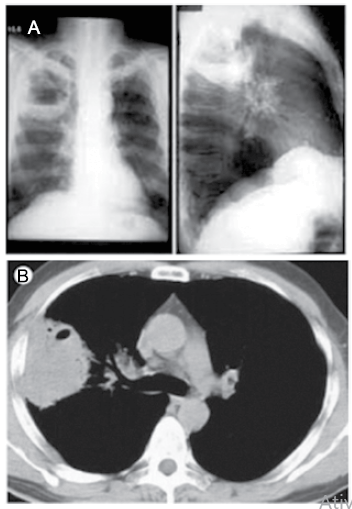

Mulher de 85 anos, portadora de distúrbio crônico da deglutição, com vários episódios anteriores de aspiração e engasgos, procurou o pronto-socorro por apresentar febre alta, tosse produtiva (“catarro espesso”), dor torácica à direita e dispneia há uma semana. Na admissão: temp. ax. 38,0 ºC, sat.O2: 90%; PA: 125x85 mmHg; FC: 98 bpm. Após as medidas iniciais de estabilização e reanimação, foram realizados exames de imagem demonstrados a seguir.

Enunciado 3161838-1

Com base nos dados clínicos e exames demonstrados, o diagnóstico da paciente é: